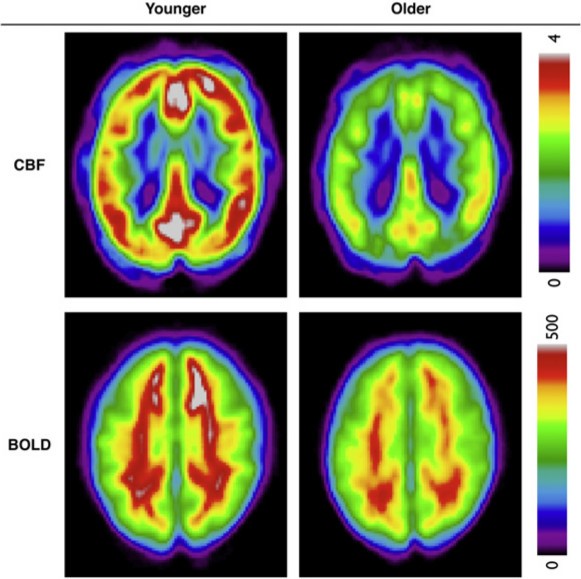

Dr. Gauthier's Quantitative Physiological Imaging Lab specializes in quantitative imaging of the cerebral vasculature using MRI and further development of these techniques. Mapping vascular processes such as cerebral blood flow and oxygenation provide quantitative insights into brain function in health and disease. Quantitative MRI methods are used in the lab to investigate links between brain ageing and cognition, how cardiovascular disease affects the brain and how the brain adapts with behavioural interventions. The long-term goal of work conducted in the lab is to improve our understanding of vascular changes across the lifespan and improve brain health in later life and disease.

- Arterial Spin Labelling (ASL): ASL enables direct quantification of cerebral blood flow without the need for tracers and is extremely valuable in studies where the brain’s vasculature may be compromised.

- Blood-oxygen-level dependent (BOLD): BOLD signal imaging is based on changes in the concentration of oxygenated haemoglobin in the brain. This method is used in calibrated fMRI along with blood flow measures to quantify additional processes such as cerebral oxygen metabolism.

- Gauthier, C. J., Madjar, C., Desjardins-Crépeau, L., Bellec, P., Bherer, L. & Hoge, R. D. Age dependence of hemodynamic response characteristics in human functional magnetic resonance imaging. Neurobiology of Aging 34, 1469–1485 (2013). doi:10.1016/j.neurobiolaging.2012.11.002

- Cerebral Hemodynamics in Aging: Effects of Fitness and Obesity